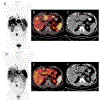

Figures